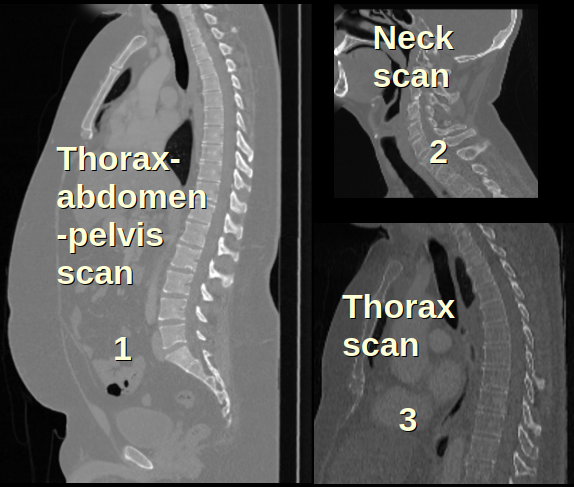

Impact of Centroid Loss

The centroid loss (CL) introduced in (4) is essential for learning common prior and robust deformations. Figure 4(b) shows the learned prior without CL, which resulted in three sets of vertebrae configurations as indicated by the arrows. These corresponds to the three common scanning positions in the dataset (thorax-abdomen-pelvis, neck, and thorax scans) as shown in Figure 4(a). Without CL, the Deform block fails to properly shift the prior to correct positions, and the learnable prior is forced to represent three vertebrae configurations. With CL, deformation prior can successfully align a unique set of vertebrae configuration to all types of scans, resulting in a much better prior.

((a)) Common scan types

Refer to caption

((b)) without

centroid loss

((c)) with

Figure 4: Impact of centroid loss. A common vertebrae configuration should be learned, while the Deform Block align the prior to right positions. (a) Three common scan types in dataset. Scans always appear at center of padded volume. (b) Without centroid loss (failed case): Deform Block fails to shift with large displacement, and learned prior are forced to adopt three vertebrae configurations. (c) With centroid loss, we can learn a prior with correct anatomy.